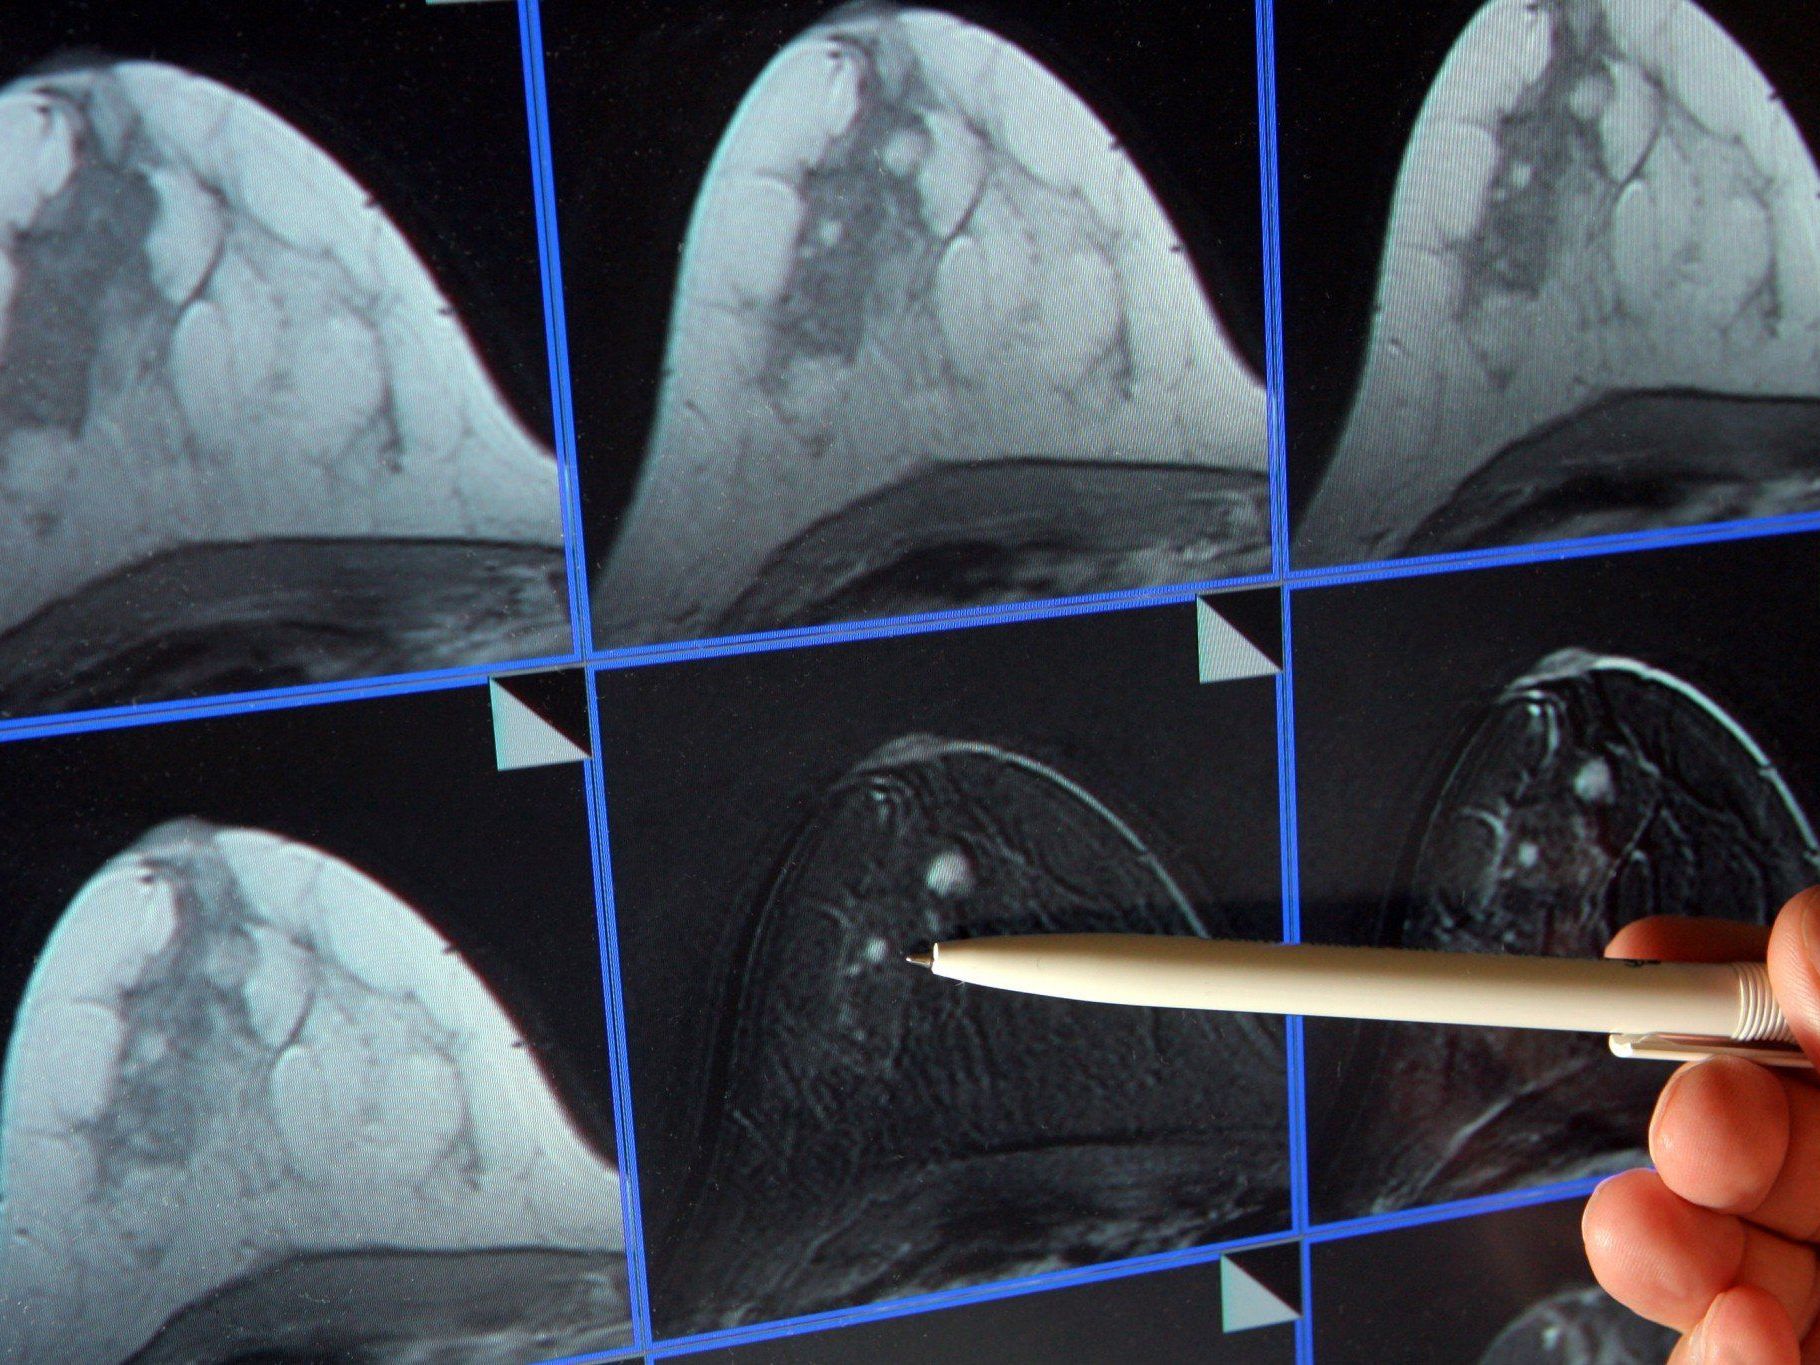

Die Tarifverhandlungen zum Brustkrebs-Screening laufen noch - Ärztekammer und GKK konnten sich noch nicht einigen.

Die Tarifverhandlungen zum Brustkrebs-Screening laufen noch - Ärztekammer und GKK konnten sich noch nicht einigen. ©dpa